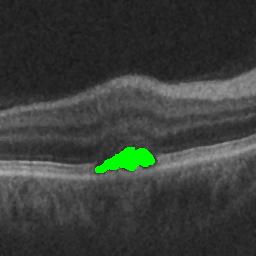

The qualitative results of the proposed system is shown in the Fig. 3. The detection task is evaluated using Area Under the Curve(AUC) metric and the segmentation task is evaluated using Dice Coefficient(DC) metric and the results are presented in Table1

| (a) De-noised OCT slice | (b)Predicted fluid region | (c)Manual fluid segmentation |

|

|

|

| (d) De-noised OCT slice | (e)Predicted fluid region | (f)Manual fluid segmentation |